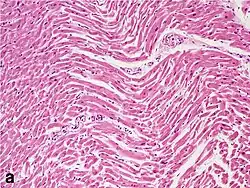

Under the microscope, myocardial infarction presents as a circumscribed area of ischemic, coagulative necrosis (cell death). On gross examination, the infarct is not identifiable within the first 12 hours.[22]

Although earlier changes can be discerned using electron microscopy, one of the earliest changes under a normal microscope are so-called wavy fibers.[23] Subsequently, the myocyte cytoplasm becomes more eosinophilic (pink) and the cells lose their transversal striations, with typical changes and eventually loss of the cell nucleus.[24] The interstitium at the margin of the infarcted area is initially infiltrated with neutrophils, then with lymphocytes and macrophages, who phagocytose ("eat") the myocyte debris. The necrotic area is surrounded and progressively invaded by granulation tissue, which will replace the infarct with a fibrous (collagenous) scar (which are typical steps in wound healing). The interstitial space (the space between cells outside of blood vessels) may be infiltrated with red blood cells.[22]

These features can be recognized in cases where the perfusion was not restored; reperfused infarcts can have other hallmarks, such as contraction band necrosis.[25]